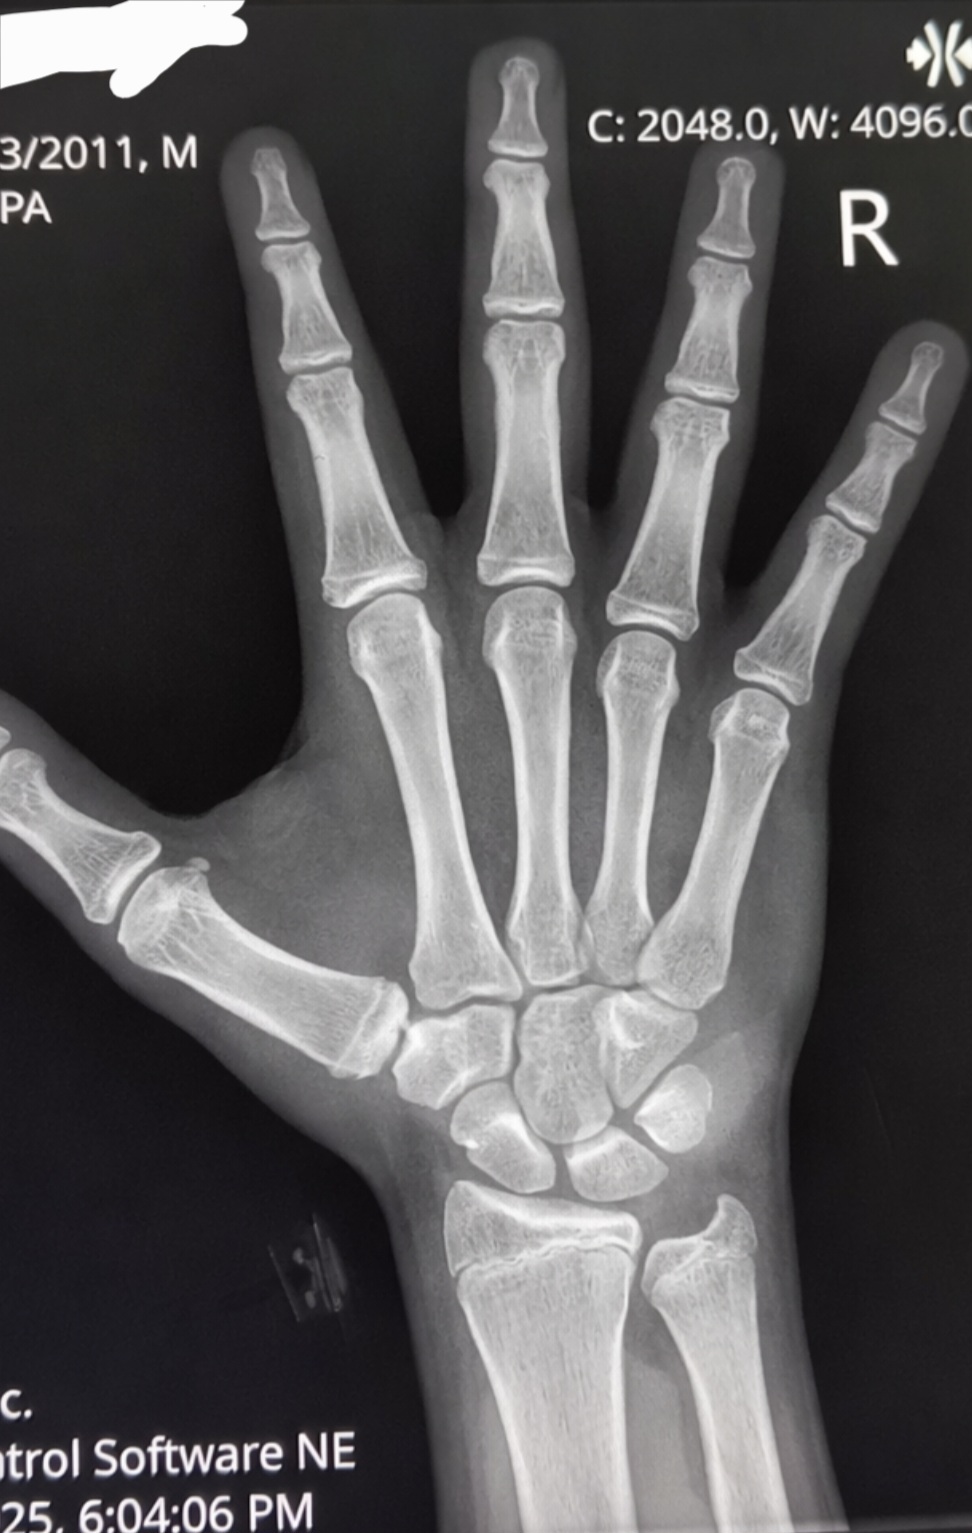

14 yr old hand x ray bone ags good or bad

im also 6'2 with a stubble beard